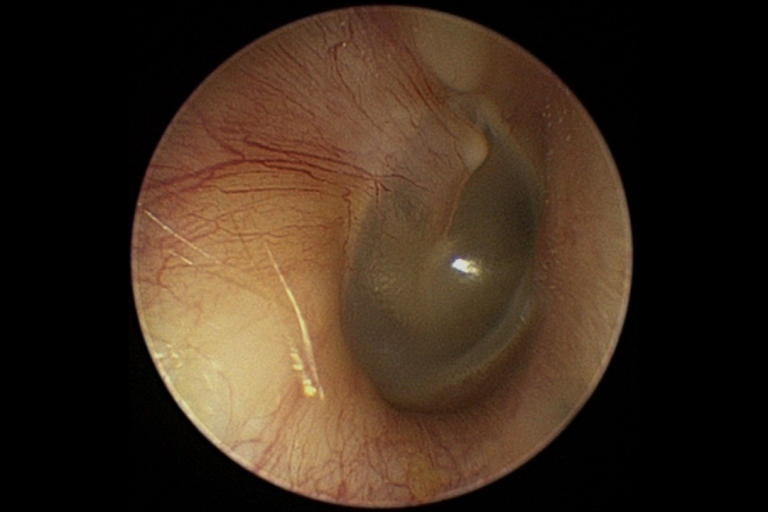

Video-Otoskopie

Durch die visuelle Inspektion des Gehörgangs können Auffälligkeiten im Ohrbereich erkennen, die möglicherweise Auswirkungen auf das Hörvermögen haben. und dabei obstruktive Faktoren wie Ohrenschmalz oder Entzündungen zu identifizieren, während die Untersuchung des Trommelfells auf Perforationen, Rötungen oder andere pathologische Veränderungen hinweisen kann.